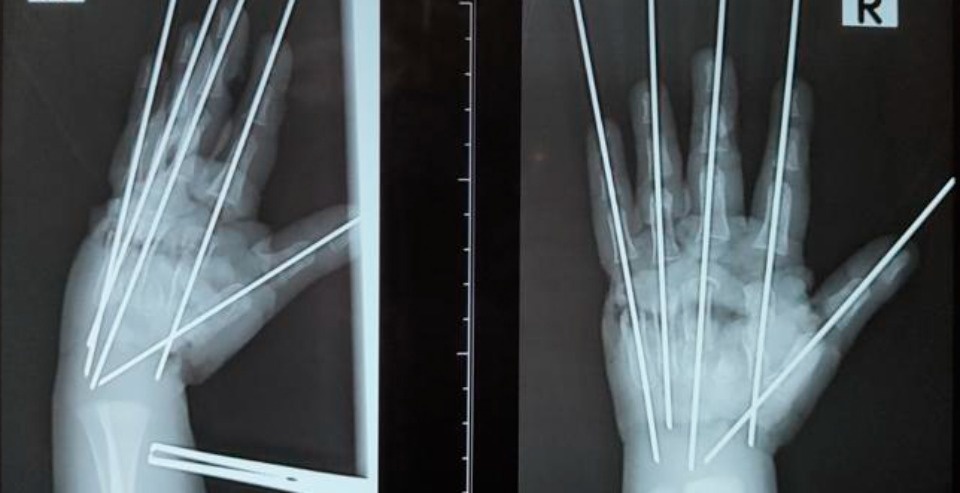

По словам врача, из-за раздавливающего механизма мясорубки травма у ребенка была тяжелой. У мальчика были раздроблены кости, сосуды, сухожилия, нервы – повреждена была вся кисть. «Фактически имела место ампутация – кисть держалась на нескольких связках. Нашей задачей было сохранить жизнеспособные ткани, восстановить анатомию конечности и кровообращение», – подчеркнул Антон Волков.

Травмированную руку в ходе операции собрали буквально по частям. Сначала врачи выполнили металлоостеосинтез для соединения осколков костей. «Затем было необходимо восстановить кровоснабжение кисти», – отметил микрохирург.